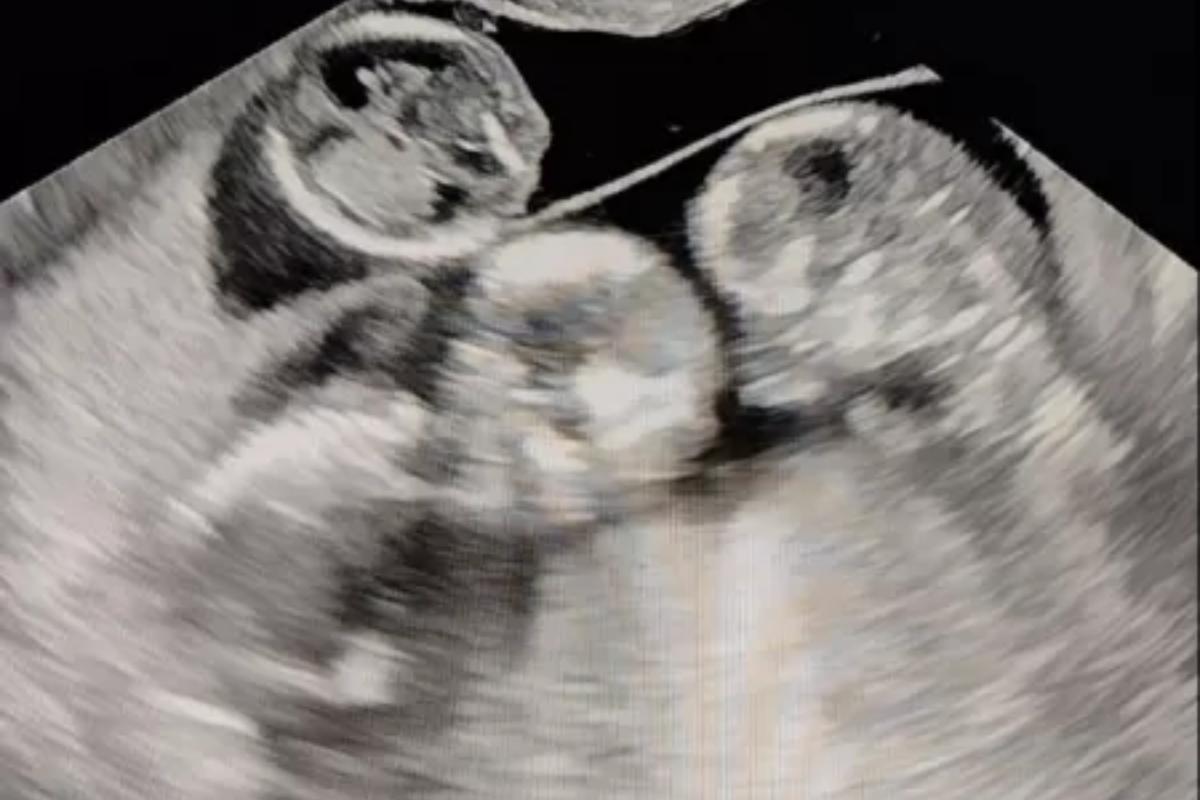

Ultrassom de Lívia Magalhães

Ultrassom de Lívia Magalhães Reprodução/Arquivo pessoal

Ultrassom de Lívia Magalhães (Foto: Reprodução/Arquivo pessoal)

Para o espanto de Lívia e seu companheiro, foi durante o exame para saber se estava tudo ‘ok’ com a inserção do DIU, que foi descoberta a gestação de trigêmeos. “Nesse exame que descobri a gravidez. A médica me perguntou: ‘Você está fazendo o exame para colocar o DIU?’ Respondi que sim. Ela falou: ‘Não vai dar para colocar. Você já está grávida’ (…) Meu noivo estava comigo na sala de exame. Tomamos um susto na hora. Nem passou pela minha cabeça porque como tomava o anticoncepcional, a chance disso acontecer era muito baixa. Eu tinha parado de tomar a pílula porque estava atacando demais a minha gastrite, mas usei preservativo nesse período. A verdade, porém, é que eu já estava grávida”, cotou.

Após o susto, a médica de Lívia disse que ela estava grávida de sete semanas, e que a gestação era de trigêmeos. No entanto, a surpresa foi se misturando ao sentimento de ‘frio na barriga’, pois, uma segunda notícia veio para abalar o casal. A gravidez em questão é de risco, fazendo com que os bebês possam nascer de forma prematura.